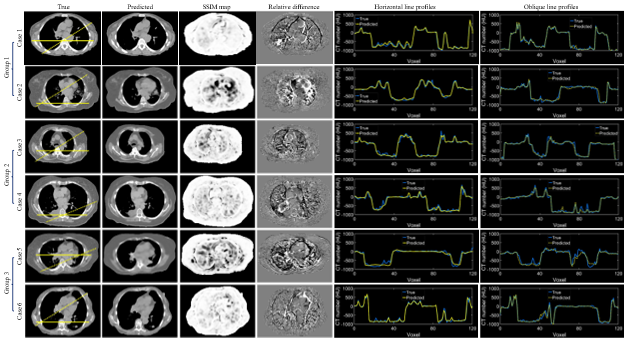

Fig. 3 depicts the violin plots to classify the evaluation results of patient images in three groups using k-means clustering[5, 29] based on MAE, PSNR, and SSIM. The figure includes probability distributions and interquartile ranges to measure the performance of the proposed method. The mean values of each metric show that the surface-volume network can generate 3D CT images with minimum uncertainty for patients in group 1 (Table 1). Fig. 4 shows the reconstructed volumetric images and ground-truth CT in transversal views for different cases from different groups. Fig. 4 also includes comparisons of SSIM, difference maps, and CT-number line profiles between synthetic images and ground truth. Fig. 5 illustrates the sagittal views of the reconstructed volumetric images, together with the ground-truth CT and histogram comparisons of CT numbers between generated images and ground truth. All evaluation metrics indicate the model potential regarding generating comparative volumetric images to 3D CT images acquired from treatment planning CT scanners. Indeed, the results indicates that the performance of deep hierarchical networks differs for patients in different groups (Fig. 3-5). The surface image datasets with high quality should increase the predictive capability as well as the learning efficacy, which potentially makes the surface-to-volume model deployable in the clinic.

Fig. 4. Examples of predicted volumetric images from each group. The transversal views of ground truth and predicted CT are displayed. The evaluation metrics include structural similarity index measure (SSIM), relative difference maps, and line profiles. The horizontal solid and oblique dot lines on the ground truth images indicate the location of profile comparisons. The training, validation, and testing datasets for each case include 1280, 160, and 160 CT images.